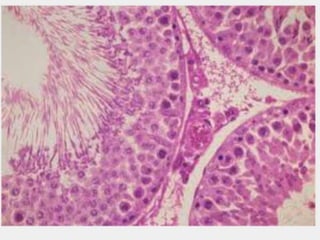

Үрийн тахир сувганцар •

Үрийн тахир сувганцрын ханыг өөрийн бүрхүүл үүсгэнэ. • Өөрийн бүрхүүл нь • Суурин • Миоид • Ширхэглэг гэсэн 3 давхаргаас тогтоно. • Өөрийн бүрхүүлийн дотор талын суурин мембран дээр сперматоген хучуур эдийн үе оршино.

14.

• Сперматоген хучуур

эд болон миоид эсийн мембраны хооронд орших суурин давхарга нь коллаген ширхгийн тороос тогтдог. • Миоид давхарга нь сийвэндээ актины филаменттай 3-5 давхар миоид эсээс тогтоно. Энэ эс нь миофибробластын нэгэн хэлбэр бөгөөд тодорхой хэмнэлтэй агшин үрийн сувганцар доторх шингэн болон спермийн урсгалыг хангана. Үрийн тахир сувганцар